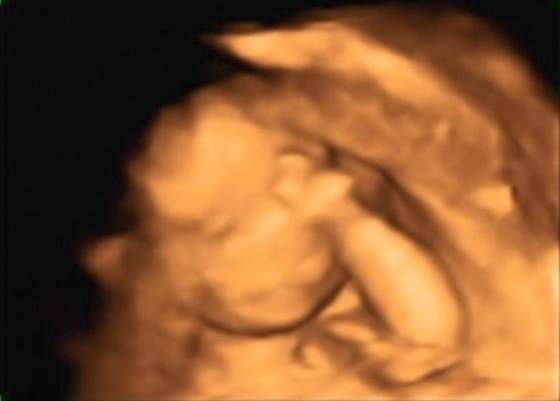

E-lona krótkie to u mnie w ramach każdej wizyty, tak ok 5 min, szybkie pomiary do szacunku wagi i kontrola przepływów. Dostaje tylko potem wydruk z pomiarami. A długie to te 3 zalecane: prenatalne, połówkowe i w okolicy 32tc i te u mnie trwają 30-40 min i wtedy dostaje duzo zdjęć i filmik

zdecydowalam sie na to badanie bo chodze do gina na kase chorych wiec nie wszystkie badania mam dokladnie porobione... nawet nie znam wagi dzidziusia:-( i do tej pory nie chciało wcale pokazac co ma pomiedzy nozkami (wstydnis

). Mam nadzieje ze na 4d rozłoży ładnie nozki i pochwali sie czym je Bozia obdarzyła